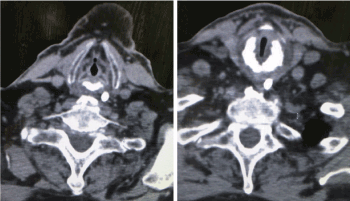

Flexible naso - endoscopy showed significant narrowing of the subglottic airway, otherwise, examination of ear, nose and throat was unremarkable. CT and MRI scans of the neck were performed which showed an infra-glottic stenosis but no mass in the upper aero digestive tract or cervical lymphadenopathy. However, there was evidence of cricoid cartilage thickening, but the radiologist did not associate this finding with any possibility of malignant change (Figures 1,2). The laryngeal airway although narrowed, was still adequate with no mucosal breaches but only thickening of the laryngeal structures and congested post-cricoid and subglottic areas.

Figure 1. CT scan of the neck of the patient with respiratory distress.